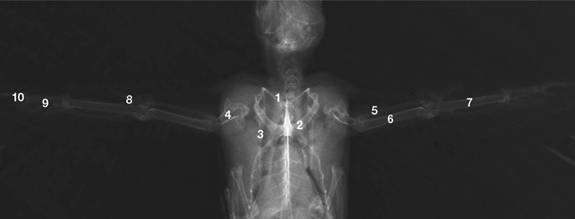

Normal anatomy of

the skeleton of a fully-grown Common Swift (shoulder girdle

and wing): 1) Clavicula, 2) Coracoid,

3) Scapula, 4)

Humerus, 5) Radius, 6) Ulna, 7) Carpometacarpus, 8) Phalanx

digiti alulae,

9) Phalanx

proximalis and 10) Phalanx distalis digiti maioris |